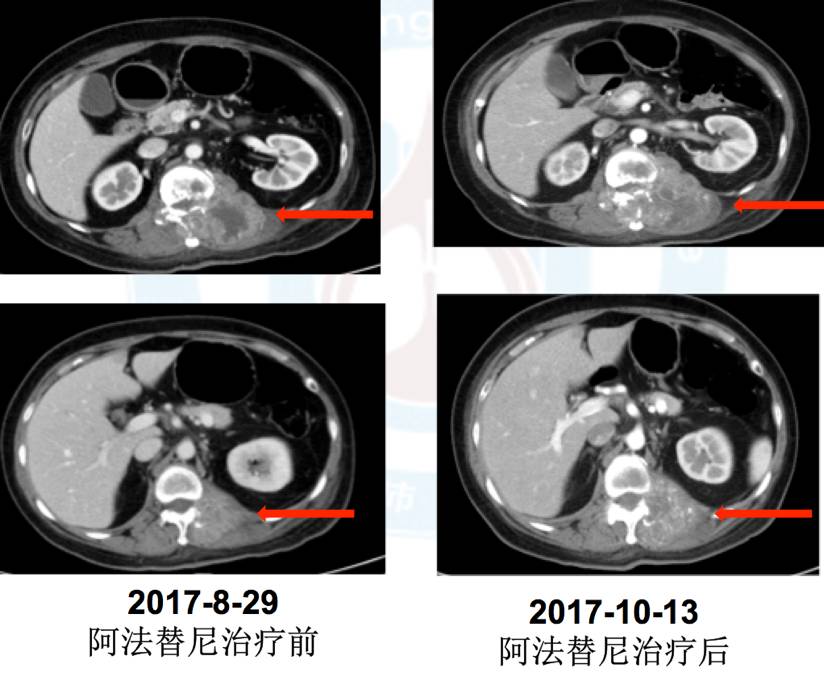

5.五线:2017年9月5日阿法替尼40mg靶向治疗,治疗1周出现I度皮疹、消化道反应,治疗45天疗效评价PD(混合疗效,部分缩小)。

肺内科李安娜医生:该患者是接受EGFR TKI治疗耐药后出现2种混合癌病理类型,这个混合癌病理类型目前考虑是肿瘤异质性引起,而不是腺癌的转化。因为最初手术切除2个肺结节病理提示是2种单纯癌组织成分,而不是混合癌成分。患者在二次肺结节穿刺活检病理提示肉瘤样癌,但给予阿法替尼治疗后部分肿瘤组织缩小,考虑缩小肿瘤组织成分为腺癌。目前患者已经是5线治疗,PS评分2分,但疼痛症状加重。既往治疗中3线治疗后,阿法替尼治疗时可以观察到部分有效。针对下一步治疗目前组内讨论意见是:因为该患者为混合性腺癌,同时存在EGFR突变,且既往阿法替尼治疗可观察到部分有效,毒副反应为轻度I度,目前已到6线治疗,无标准治疗方案,可以考虑靶向治疗联合化疗;病理为腺癌合并肉瘤样癌,可以选择泰素联合阿法替尼,间插治疗。